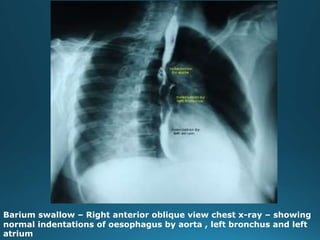

Barium swallow – Right anterior oblique view chest x-ray – showing

normal indentations of oesophagus by aorta , left bronchus and left

atrium

• 30.

Barium swallow –Right anterior oblique view chest x-ray – showing normal indentations of oesophagus by aorta , left bronchus and left atrium